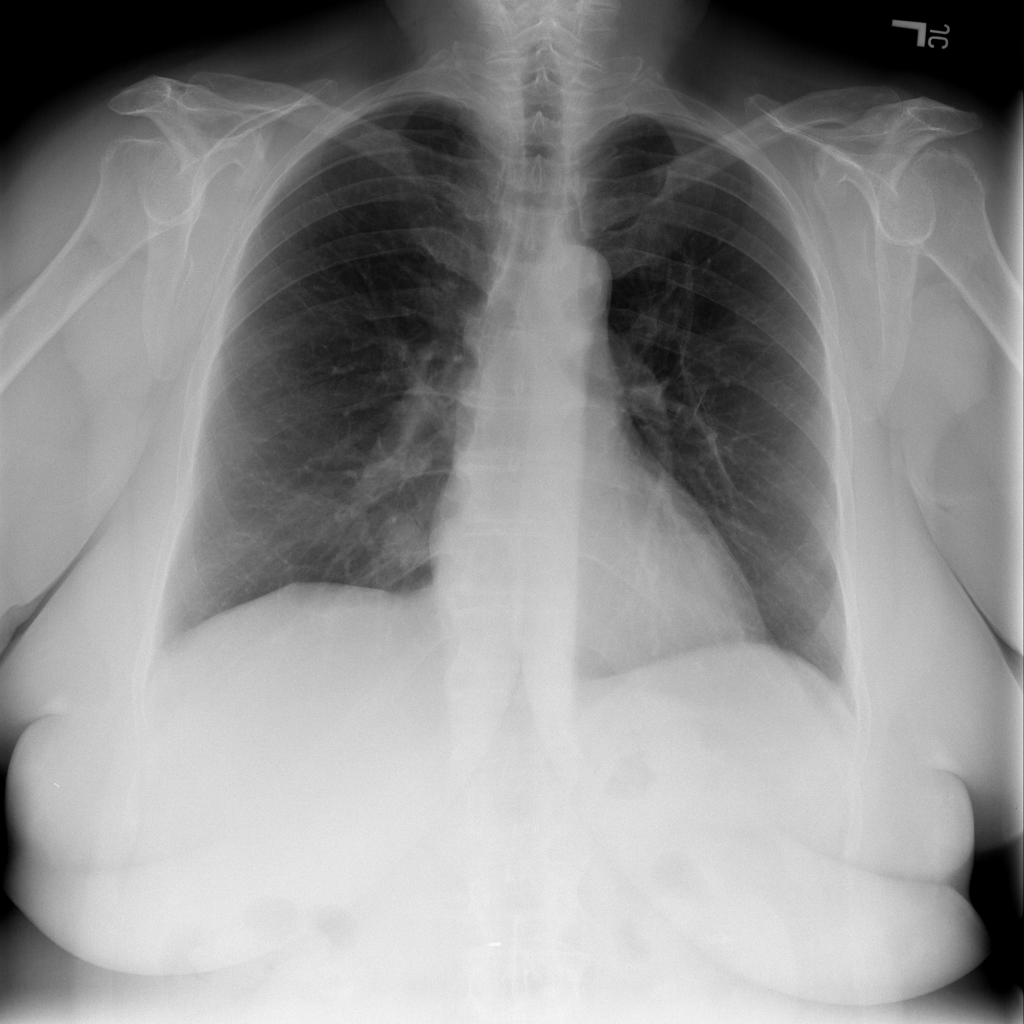

Showing up to 90 reference images for Nodule.

PAT-F3E7 · IMG-002Nodule

PAT-F3E7 · IMG-002

PA